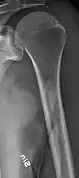

X-ray of the forearm, with lytic lesions

Multiple myeloma in the upper arm

Femur with multiple myeloma lesions

Same femur before myeloma lesions for comparison

The diagnostic examination of a person with suspected multiple myeloma typically includes a skeletal survey. This is a series of X-rays of the skull, axial skeleton, and proximal long bones. Myeloma activity sometimes appears as "lytic lesions" (with local disappearance of normal bone due to resorption) or as "punched-out lesions" on the skull X-ray ("raindrop skull"). Lesions may also be sclerotic, which is seen as radiodense.[70] Overall, the radiodensity of myeloma is between −30 and 120 Hounsfield units (HU).[71] Magnetic resonance imaging is more sensitive than simple X-rays in the detection of lytic lesions, and may supersede a skeletal survey, especially when vertebral disease is suspected. Occasionally, a CT scan is performed to measure the size of soft-tissue plasmacytomas. Nuclear Medicine Bone scans are typically not of any additional value in the workup of people with myeloma (no new bone formation; lytic lesions not well visualized on nuclear bone scan).